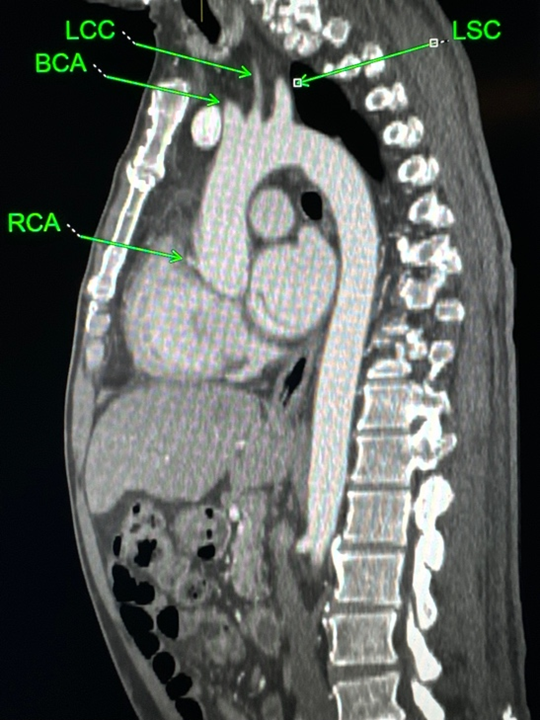

With expanding transcatheter aortic valve implantation (TAVI) indications, post-intervention cerebrovascular accidents (CVA) remain a significant concern.3 To mitigate this risk, 1 distal embolic protection device (EPD) (Sentinel, Boston Scientific) has been approved for use in the United States, and several more are undergoing various stages of development and approval. Some of the third generation TAVI EPDs in use outside the United States and currently in trials in the United States use centrifugal forces to ensconce the filter against the greater aortic curvature, thereby covering the takeoff plane of the major aortic arch branches. The device’s anchoring probe extends forward and downward, ending in the aortic root (Figure 1). Based on our findings, we suspect that this probe should be in close proximity to the RCA origin. Thus, the objective of this study was to determine if the RCA takeoff is in the same plane as the takeoff plane of the MAAB.

Chest computed tomographic angiography (CTA) images (TAVI protocol) were used to form a double oblique plane using free manipulation of the standard axial, coronal, and sagittal planes. We started in the standard axial plane at the aortic root approximately at the level of the RCA takeoff. Then, we used the coronal plane to tilt the axial plane approximately parallel to the aortic annulus. Next, we adjusted the new oblique axial and coronal planes to visualize the MAAB and RCA takeoffs in the oblique sagittal plane. Cases were considered positive when the MAAB and RCA takeoffs were identified in same oblique sagittal plane (Figures 2 and 3).